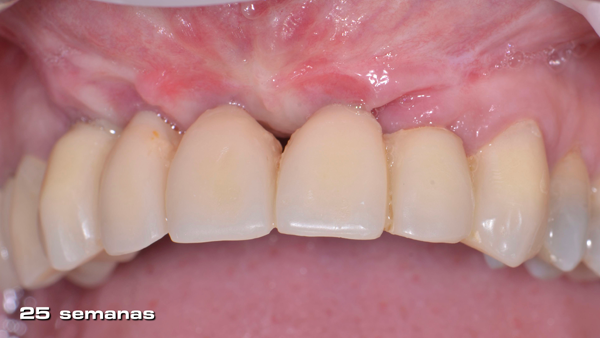

Uma vez que a membrana foi completamente fixada, o retalho foi mobilizado para permitir o fechamento primário livre de tensão. O retalho foi suturado em duas camadas: primeiro, as suturas horizontais em colchoeiro e, depois, as suturas simples para fechar as bordas do retalho (Figura 10). As suturas simples foram removidas 14 dias após a cirurgia e as suturas em colchoeiro horizontais foram removidas três semanas mais tarde. A membrana foi então removida após 25 semanas de cicatrização usando um retalho crestal de espessura total (Figuras 11 a 14).